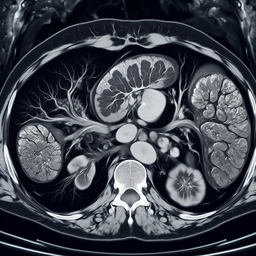

МРТ селезінки

МРТ селезінки – це неінвазивний метод візуалізації, що використовує магнітні поля та радіохвилі для отримання детальних зображень цього органу. Він допомагає в діагностиці та оцінці різних патологій, таких як травми, пухлини, кістозні утворення, запальні процеси або збільшення селезінки.